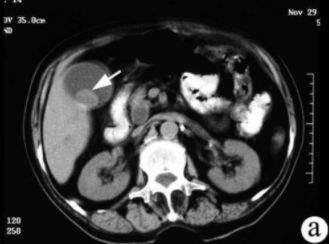

膽結(jié)石癥是膽道系統(tǒng)的常見病變,發(fā)病率為8%以上。按化學(xué)成分可將膽石分為3種類型:膽固醇類結(jié)石,膽固醇含量占80%以上;膽色素類結(jié)石,膽固醇含量少于25%;混合類結(jié)石,膽固醇含量占55%~70%。在我國以膽色素結(jié)石為主。 膽囊結(jié)石的CT表現(xiàn): CT的密度分辨率高,更有利于膽結(jié)石的發(fā)現(xiàn)。膽石的CT表現(xiàn)與其化學(xué)成分密切相關(guān),其CT值與膽固醇含量呈負(fù)相關(guān),與膽紅素和鈣含量呈正相關(guān)。

CT表現(xiàn)主要有:高密度結(jié)石(均勻或不均勻);略高密度結(jié)石;等密度結(jié)石,與膽汁密度相等平掃不易區(qū)分;低密度結(jié)石;環(huán)狀結(jié)石。